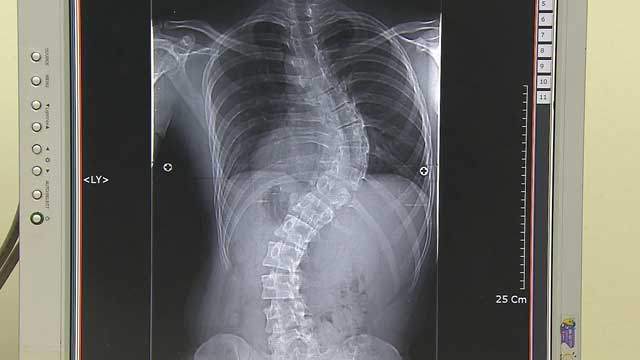

▷박광식: 척추가 C자나 S자로 휘는 척추측만증이 있으면 모두 치료를 받아야 하는 건가요?

▶서승우: 각도가 20도 미만일 때는 운동, 스트레칭 정도 하면서 관리를 하고요. 적극적인 치료개념보다는 더 휘지 않도록 바른 자세하고 스트레칭해주는 예방적 개념으로 생각하면 됩니다. 20도 이상 되면 계속 휘어질 가능성이 조금 있거든요. 그러다 보니까 20도 이상이면 보조기를 채우고요. 40도 이상이면 성인이 돼서도 계속 조금씩 휠 수 있기 때문에 한 40~50도 넘어가면 수술도 고려하게 됩니다.

▶서승우: 그렇지 않습니다. 척추측만증의 80%가 원인을 모르는 특발성 척추측만증입니다. 여성이 특히 많은데요. 관절이 휘는 질환들이 보통 여성이 많습니다. 엄지발가락이 휘는 종무지외반증이라는 것도 보통 하이힐 신어서 휜다고 많이 생각하시는데 꼭 하이힐이 원인은 아니고요. 여성에게 많이 있고 또 다리 휘는 것도 할머니들 보면 오자형 다리가 많이 있습니다. 그리고 신생아에서 고관절 빠지는 것도 보면 여아가 훨씬 더 많습니다.

▷박광식: 지금까지 건강 365 포인트 쏙쏙이었습니다. 척추측만증 치료와 수술을 결정하는 데 있어서 굽은 정도와 함께 성장상태를 고려해야 한다는 거 기억해 두면 좋겠습니다.